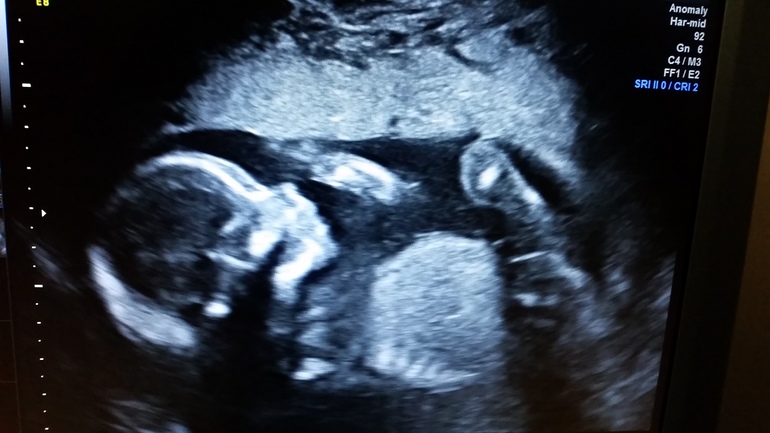

2ой скрининг

Завтра 21я неделя, прошли второй и видимо последний обязательный скрининг.

Бэбик руками тела лицо постоянно и перевернулась опять на попу. Плацента по передней высоко.

Совсем не мучают меня в этот раз больницами. Красота! Ну и пухляш :

Ого, на весь экран поместился! Мне только мордашку сделали))) Поздравляю со вторым скринингом! Примилейший малыш! Т-т-т на вас)))

Спасибо )) да там датчик 14.5 см в радиусе ) больше узи не будет. Только если платно